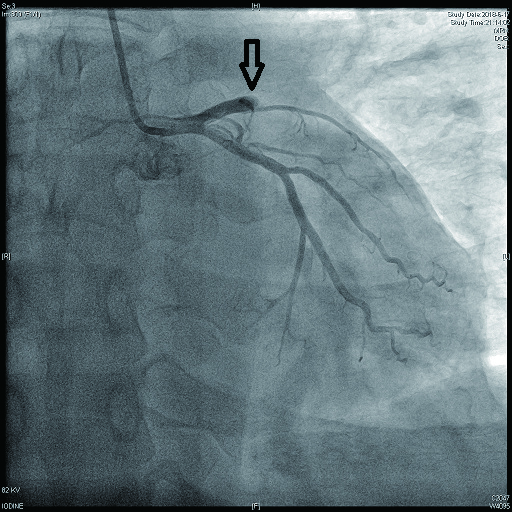

病例2 3(图 6~8 LAD近段 次全闭塞 2级 LAD近段植入支架1枚

图 6 病例2冠脉造影示LAD中段病变

图 7 病例2冠脉造影示LCX病变

图 8 病例2冠脉造影示RCA病变